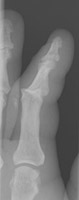

- Click on the image for a larger versionBPA and oblique radiographs of the hand. The also show the fracture of the fourth proximal phalanx.